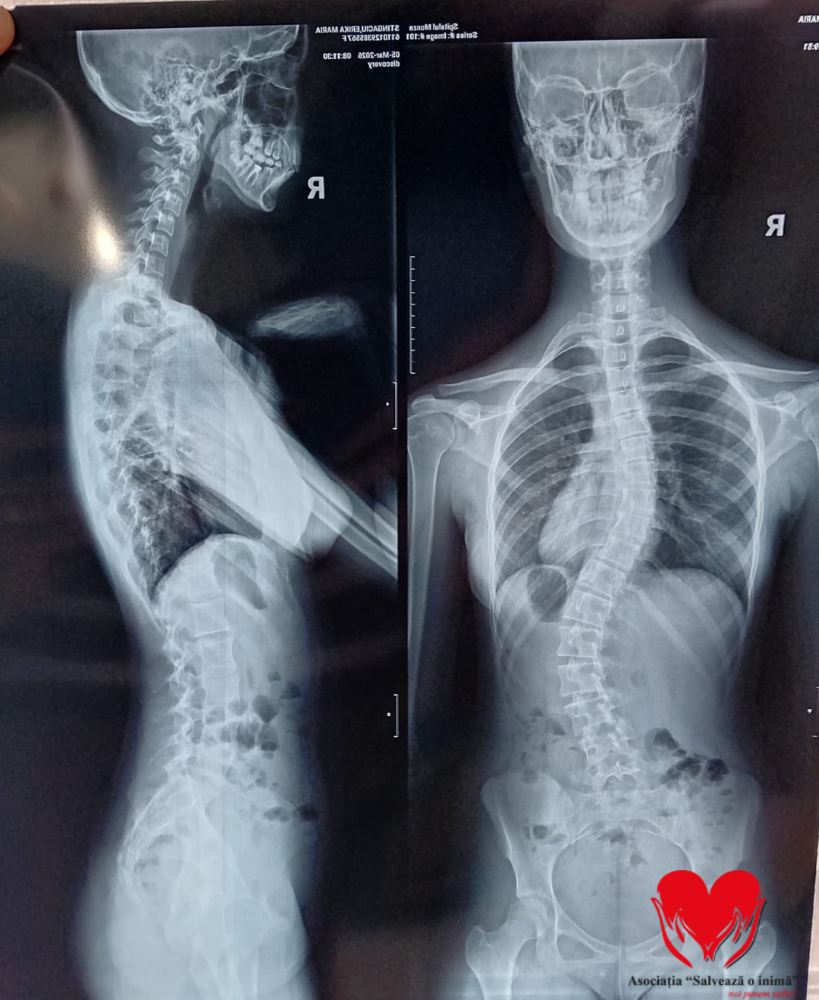

Erika Maria Stîngaciu este o adolescentă de 15 ani care se confruntă cu un diagnostic sever de scolioză dorsolombară progresivă, o afecțiune care îi modifică zilnic postura și îi afectează profund calitatea vieții. Până în urmă cu doi ani, Erika era un copil obișnuit, cu planuri simple și o copilărie trăită firesc. Totul s-a schimbat în februarie 2024, când, în urma unui consult aparent banal, medicul a observat o asimetrie la nivelul umerilor. Investigațiile ulterioare au condus la stabilirea diagnosticului de scolioză idiopatică lombară, iar de atunci viața ei a devenit o luptă continuă pentru a încetini evoluția afecțiunii.

A urmat zilnic ședințe de kinetoterapie, a purtat un corset rigid tip Cheneau timp de 23 de ore din 24 și a trecut prin multiple consultații și investigații în centre medicale din țară. În ciuda tuturor eforturilor, evoluția a continuat, iar în februarie 2026, în urma unui nou control, medicii au confirmat caracterul progresiv al scoliozei și necesitatea unei intervenții chirurgicale. „Fiecare zi simt cum spatele meu se schimbă și devine tot mai greu să stau dreaptă. Corsetul mă ajută, dar nu oprește ceea ce se întâmplă. Îmi doresc doar să pot merge la școală fără durere și fără teamă, să fiu ca ceilalți copii. Operația este șansa mea, vă rog din suflet, ajutați-mă.”- spune Erika Maria Stîngaciu.

În prezent, Erika continuă să poarte corsetul zilnic și să urmeze terapii, însă acestea nu mai pot opri evoluția deformării coloanei. Singura soluție rămasă este intervenția chirurgicală, care îi poate reda șansa la o viață fără durere și fără limitările actuale.